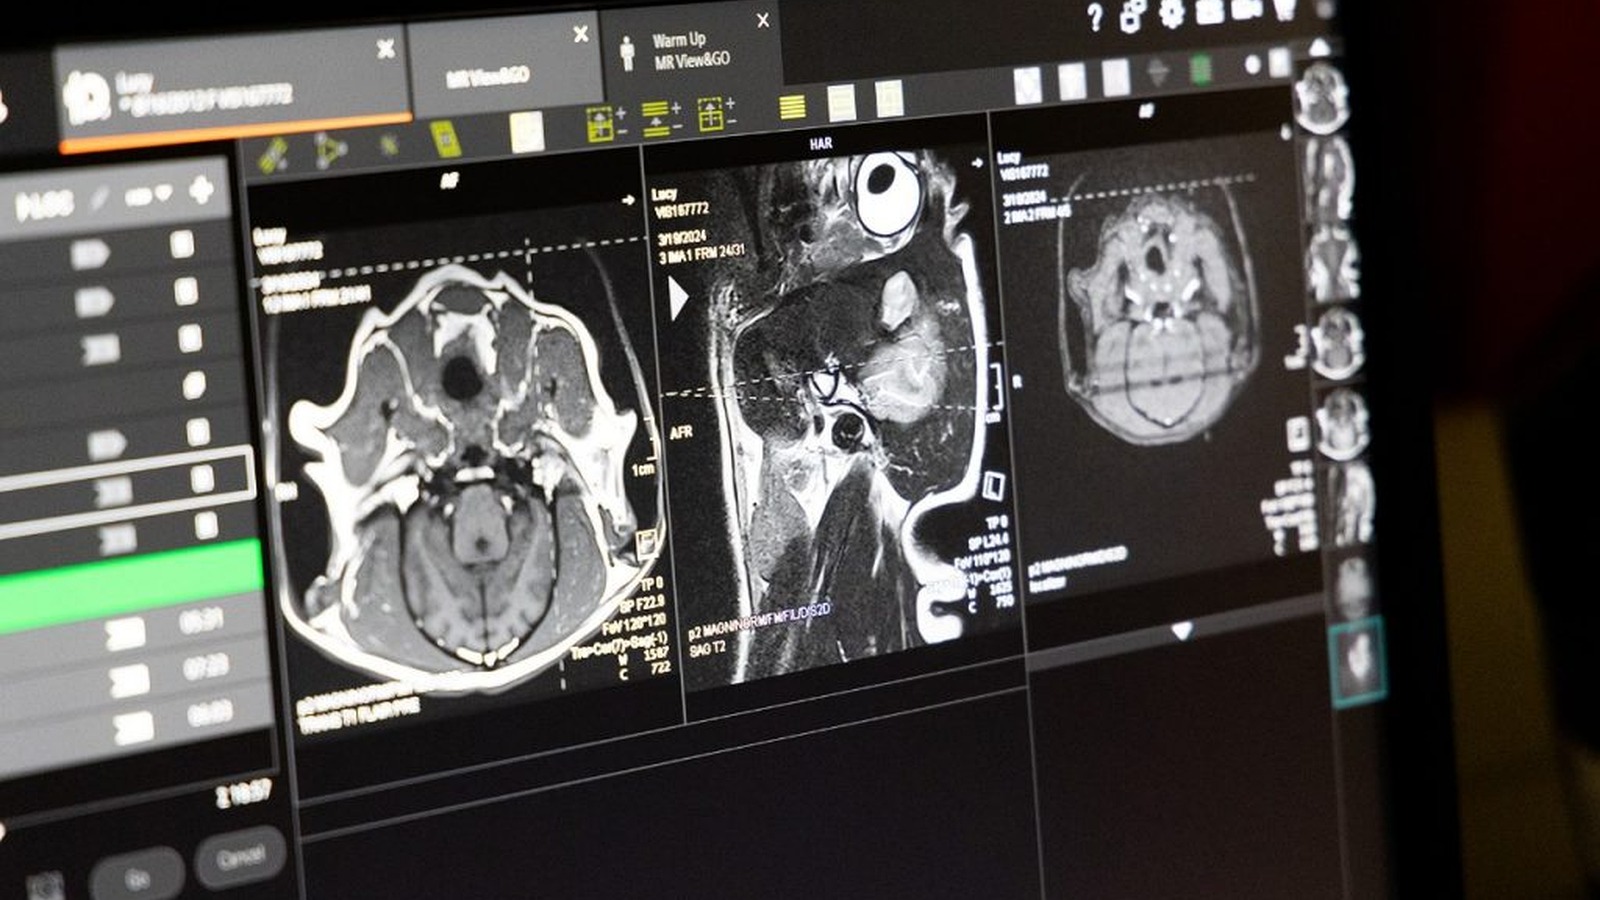

Veterinary Radiologists

Veterinary Neurologists